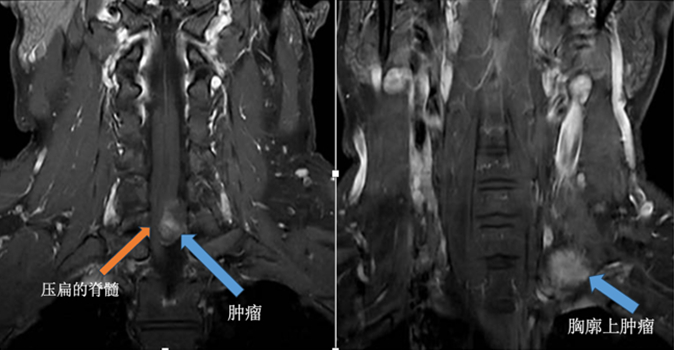

患者李哥(化名)是一名35岁的男性患者,因为连续10个月出现腰痛伴双腿酸痛的情况,到深圳市人民医院进行了CT及核磁检查。检查结果显示,李哥颈椎管内有一个呈哑铃型的异常占位,从椎管内突破至胸腔内,内小外大。

医生经过研判,考虑该异常占位为椎管内哑铃型神经鞘瘤,需尽快手术。但由于肿瘤形状特殊,传统的手术要考虑开胸手术才能切除肿瘤,需要先从李哥的椎体后方切开一个创口,先切除椎管内的肿瘤,然后再从颈部切开一个创口,切除从椎管内突出到颈部的肿瘤。这样一来,手术需要两个大切口,可能还需要分次进行手术,手术时间长,创伤大,恢复慢,对患者围术期的生活质量也有所影响。